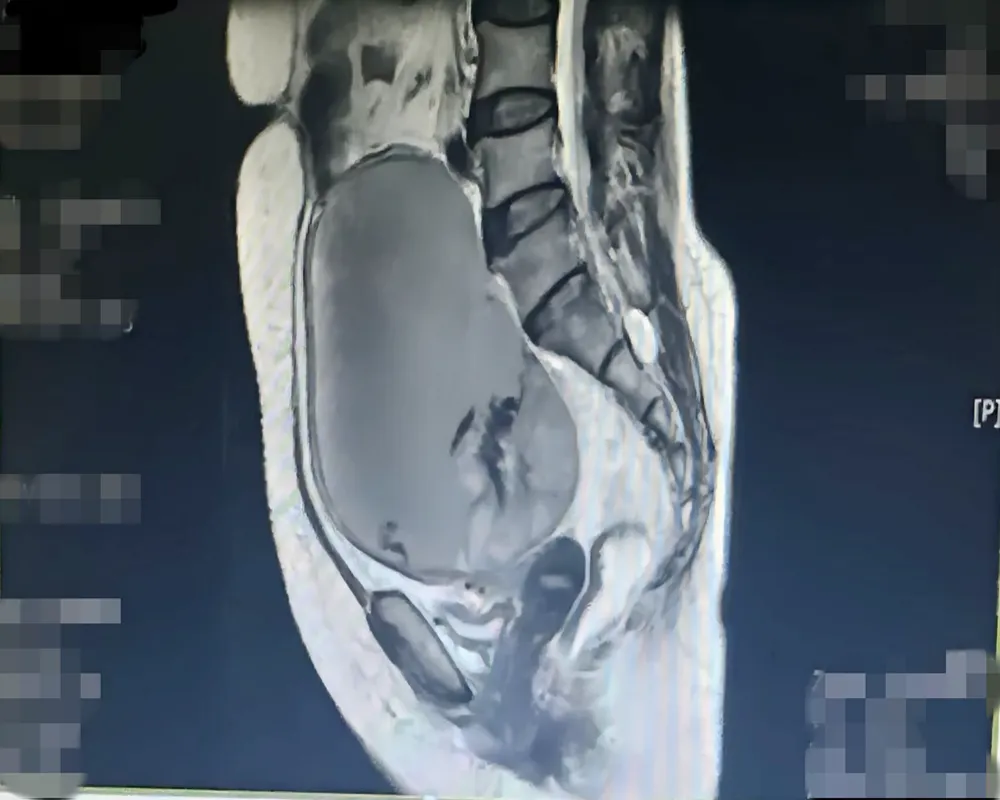

▲患者影像资料